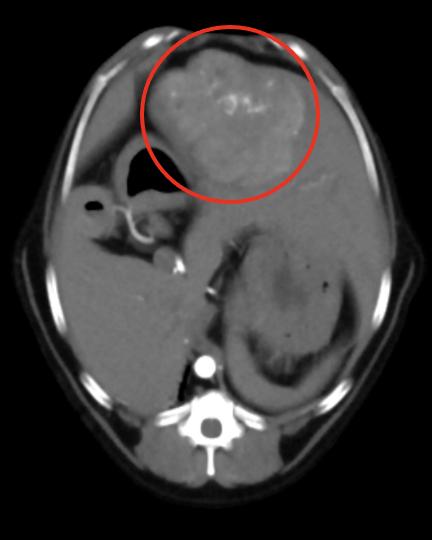

| ケース | 10歳8ヶ月、避妊済みの女の子、ワンちゃん |

| 症状 | 3日前より食欲不振と嘔吐、下痢を主訴に来院されました。腹部触診にてお腹のなかにしこりが触知されました。エコー検査を行ったところ、左上腹部に腎臓腫瘍が認められました(図1)。オーナー様とご相談の上、摘出することにしました。 |

| 手術方法 | 全身麻酔下で開腹を行い、腎臓腫瘍の摘出を行いました(図2~3)。また、同時に膀胱内結石の摘出も行いました(図4)。 |

| 術後経過 | 腎臓腫瘍を病理検査に出したところ“腎細胞癌”との結果でした。腎細胞癌は極めて悪性度の高い腫瘍です。術後、抗癌剤治療を行うなど、大変よく頑張ってくれましたが、手術から8か月後に残念ながら亡くなってしまいました。 |

| 図1 | 図2 | 図3 |